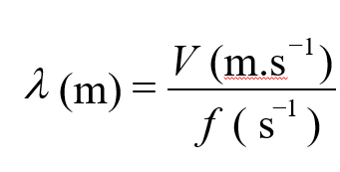

Wavelength

The wavelength is the distance traveled by the sound during a single cycle, or between two identical points in the cycle of the wave. It is the distance between two points of compression peak that follow one another. Please note that the frequency and the wavelength are inversely proportional, when the frequency increases, the wavelength decreases, and vice versa.

The wavelength (l) and the frequency (f) are connected by the below formula:

Find below the different wavelength values of the ultrasound wave while it passes through some organs and tissues.